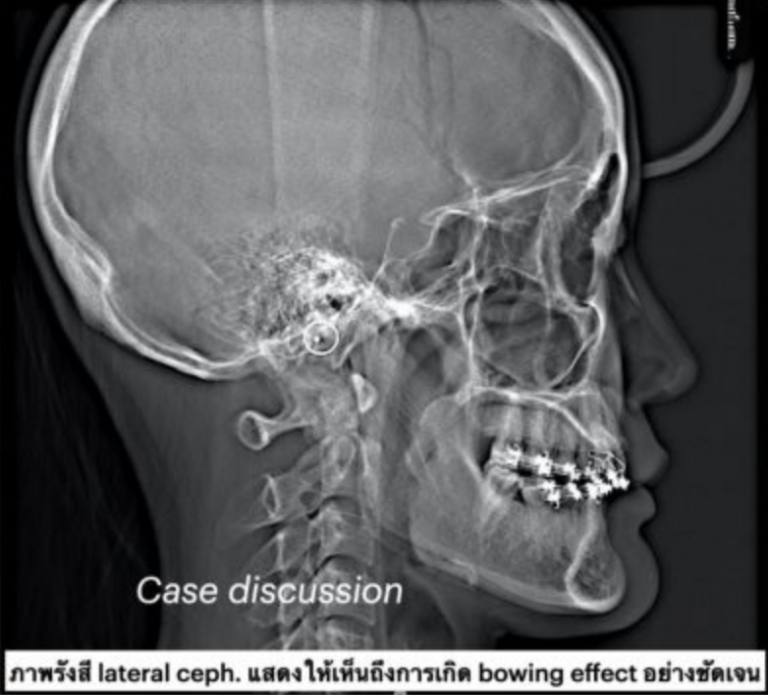

ตัวอย่างผู้ป่วยรายที่1

ตัวอย่างผู้ป่วยรายที่2

ตัวอย่างผู้ป่วยรายที่3

อย่างไรก็ตามแม้ว่าเทคนิคดังกล่าวนี้จะให้ผลดีต่อการเคลื่อนฟันจริงตามผลการศึกษาต่างๆ แต่ทันตแพทย์ก็ต้องเลือกเคสอย่างเหมาะสม เพื่อป้องกันcomplicationอื่นๆที่อาจเกิดขึ้นภายหลังการผ่าตัดได้ และถึงแม้ว่าการทำPAOOจะเพิ่มระยะlimits of tooth movementจากenvelope of discrepancyได้ก็ตาม แต่ก็ไม่สามารถเคลื่อนฟันได้แบบไร้ขีดจำกัด เคสใดที่มีความผิดปกติของขากรรไกรมาก ก็ยังคงแนะนำให้จัดฟันร่วมกับการทำorthognathic surgeryอยู่ดี